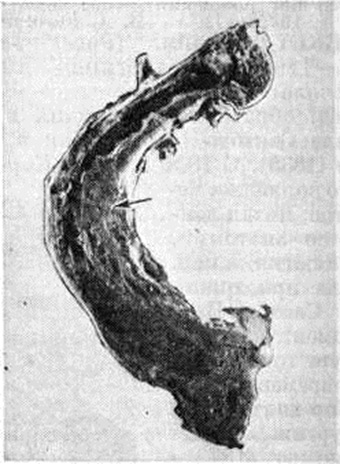

В позвоночнике изменения локализуются в теле и дуге одного или нескольких, смежных или близко расположенных позвонков. В процесс вовлекаются крестцовые, грудные или поясничные, реже шейные позвонки. Весь позвоночный столб никогда не поражается. Изменённые позвонки увеличиваются, передняя и боковые поверхности их сглаживаются. Нередко они сплющиваются, выдвигаясь за пределы нормальных границ позвоночного столба, деформируя позвоночный канал и межпозвоночные отверстия. На распилах (рисунок 3) структура позвонков неоднородная, участки разрежения чередуются с груботрабекулярными тяжами, более компактны их периферические отделы (рентгенологически — трабекуляризация, рисунок «рамы»). Местами костная ткань принимает вид мелкозернистой пемзы. Патологически изменённая костная ткань может замещать межпозвоночные диски, поверхность которых становится как бы изъеденной (рисунок 4). Возможно преобразование смежных сегментов в однородную функционально недифференцированную костную ткань. Опорная функция позвоночника снижается, возникают осложнения, обусловленные сдавлением спинного мозга и спинномозговых нервов.